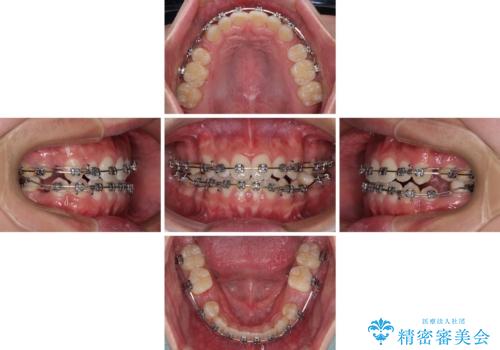

口元の突出感を改善 受け口傾向の咬み合わせの抜歯矯正

- メタルブラケット

下顎の残存乳歯は小臼歯よりも大きいため、スペースを閉じるために長い期間を必要としますが、予想通りに長期間を要することとなりました。

受け口傾向の方の抜歯矯正は、下顎前歯が舌側に倒れることで歯肉退縮を起こしやすいことが知られていますが、ワイヤーに工夫をすることでリスクを軽減させています。